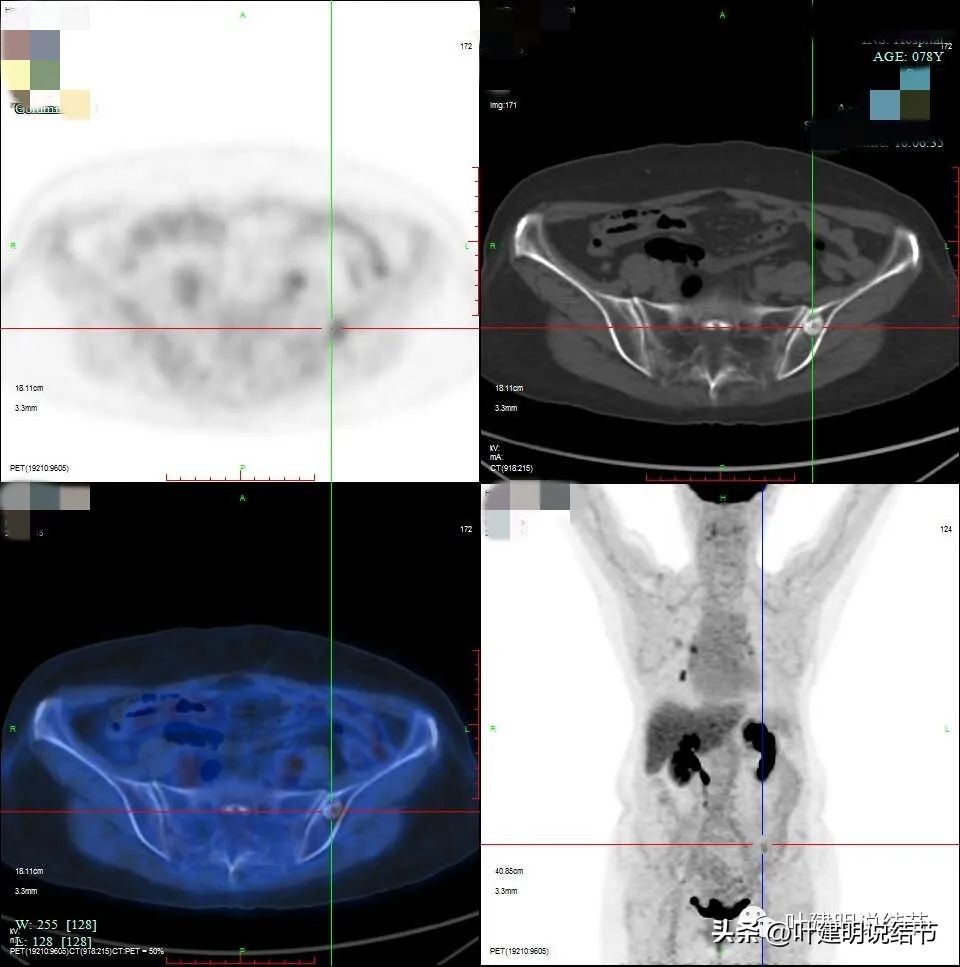

PET说右上后段考虑恶性病变。右肺门区,即上述说肺动脉上方的淋巴结是考虑转移可能性大,但没有说纵隔内的淋巴结有异常高摄取。还是就是左侧髂骨内结节样不均匀稍高密度影,葡萄糖代谢增高,要考虑良性肿瘤或肿瘤样病变可能性大。

上图是骨骼异常处。

所以做了骨骼的MRI检查,结果如下:

考虑良性可能性大。